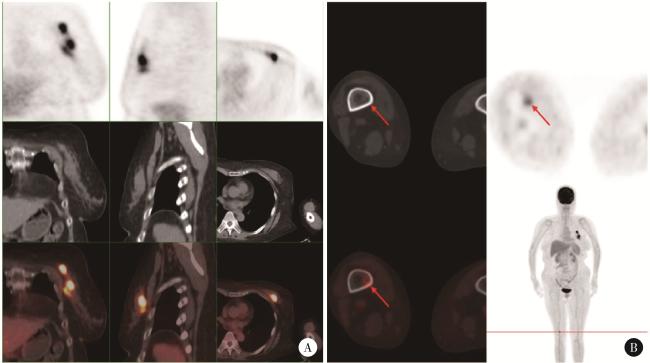

图1 患者PET/CT检查结果(2023年10月)Figure 1 PET/CT images of the patient (October 2023) A, left breast, multiple foci of increased flurodeoxyglucose (FDG) metabolism with a maximum standardized uptake value (SUVmax) of 10.1; B, right femur (distal), increased FDG metabolism with an SUVmax of 4.6. |